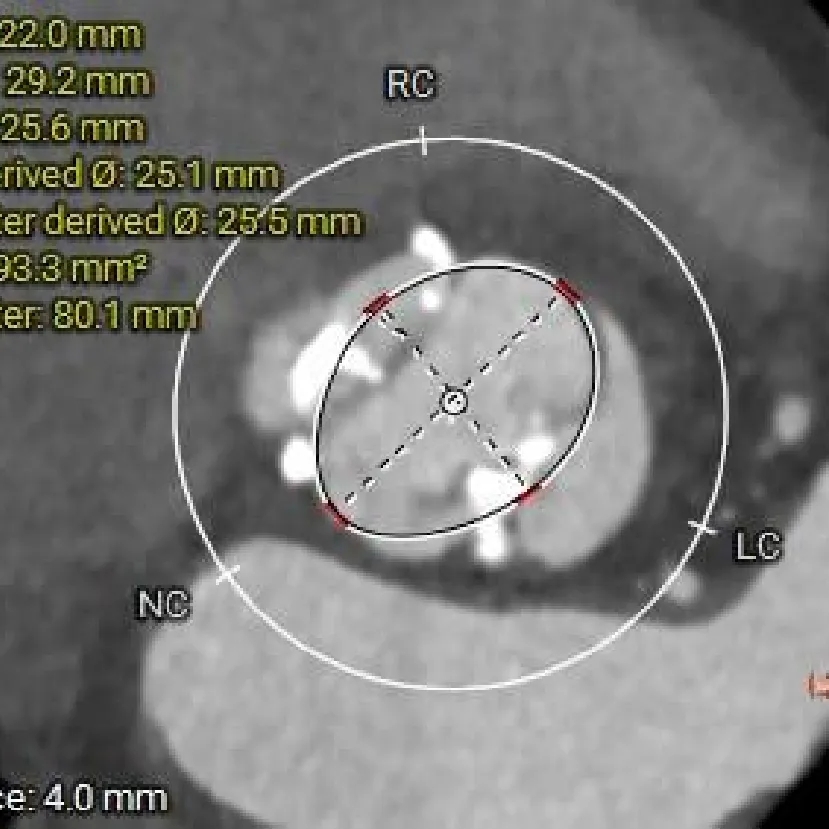

瓣上4mm

25.5mm